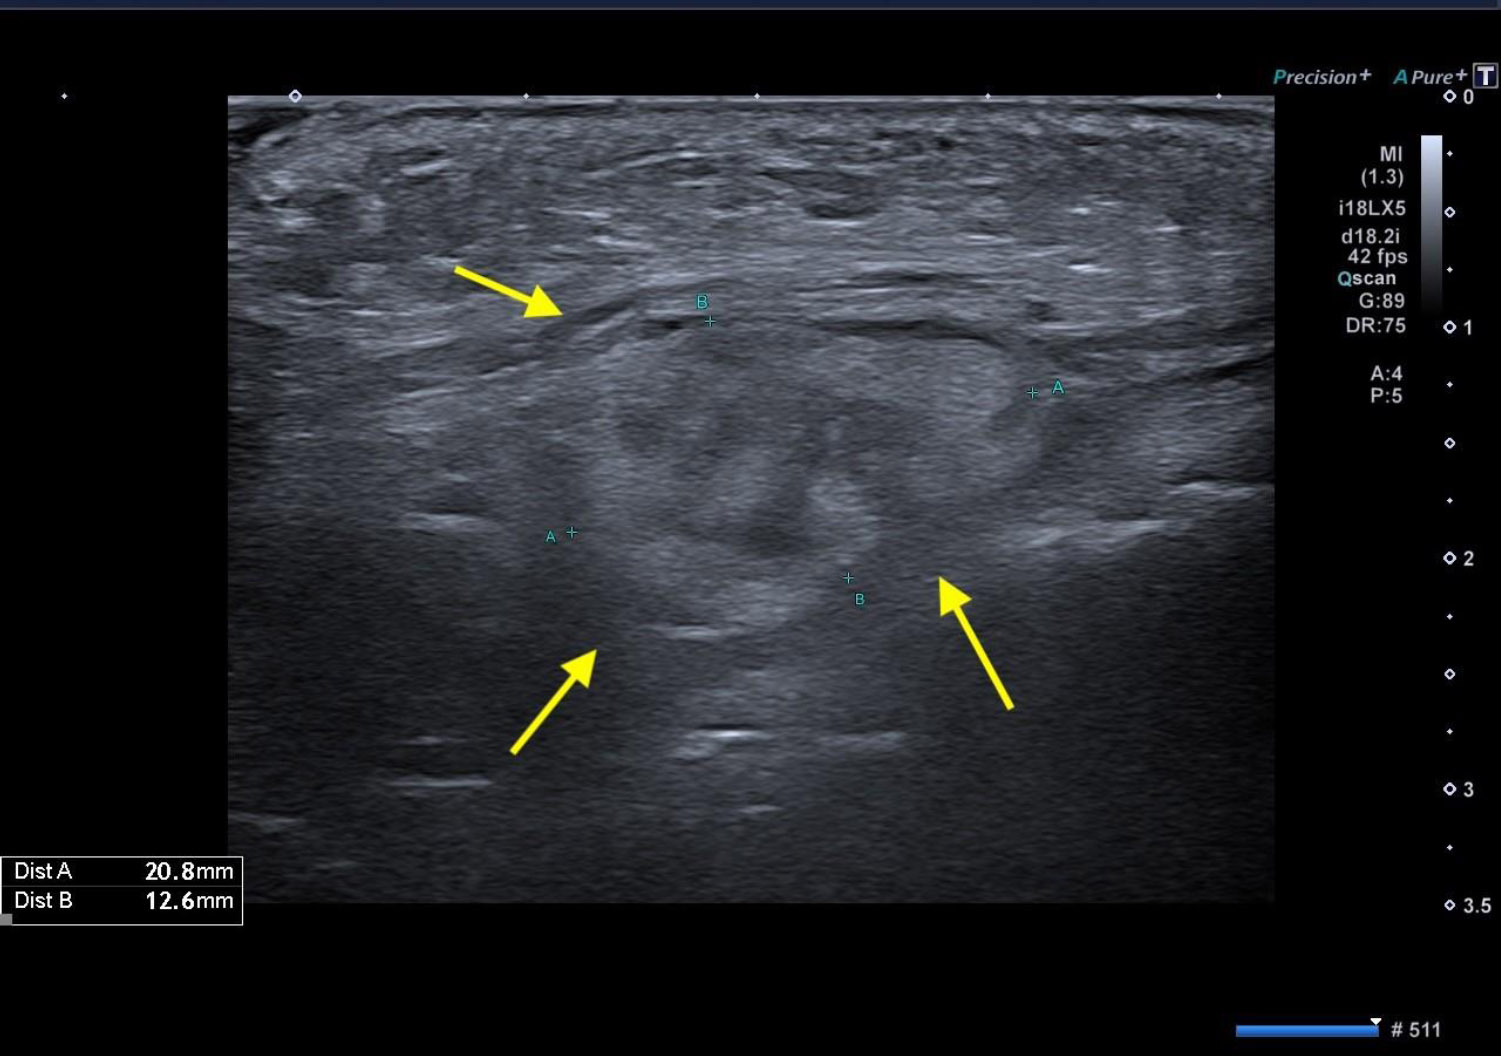

With the patient’s consent, X-rays were performed. Orthopanoramic images showed no macroscopic alteration of the bony structures, whereas an intraoral radiograph revealed a radiolucent apical lesion on tooth 2.6, suggesting a possible diagnosis of odontogenic abscess (Fig. 2). Therefore, a new antibiotic therapy (clindamycin 900 mg a day for 6 days) was prescribed, and an echography was scheduled for a more detailed evaluation of the swelling. The patient was re-evaluated three days later, showing no signs of improvement. The ultrasound showed a profound alteration in the intramuscular portion of the left cheek (buccal space), with a 3x2 cm central inhomogeneous portion with irregular and blurred edges. This central area was surrounded by a hyperechoic halo, suggesting a granulomatous reaction (Fig. 3). After further investigating the medical history and conducting an additional interview with the patient, it was found out that she had previously undergone a treatment with ozonized sunflower oil (Ozosan Gel, Bioactiva, Vicenza, Italy) used locally, after the use of anesthesia. Thus, the possibility of an off-label periapical injection of ozonized oil was considered. Only an injection administered coronal to the upper insertion of the buccinator muscle could explain the accumulation in the cheek.

Initial echography. The presence of a 3x2 cm central inhomogeneous portion with irregular and blurred edges, surrounded by a hyperechoic halo (yellow arrows), suggesting a granulomatous lesion.